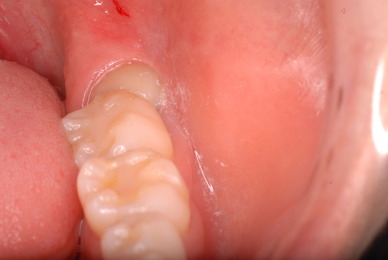

歯周病の疑いで東京のかなり遠方の方が来院されました。

驚くべきことですが、定期検診は受けていたそうです。しかしながら歯周病の指摘は受けたことがないそうです。

何故か?定期検診が虫歯のチェックのみになり、又肝心の歯周病の検査や歯周病の部分の予防や治療のためのブラシの使い方などを学んだ事がないのです。